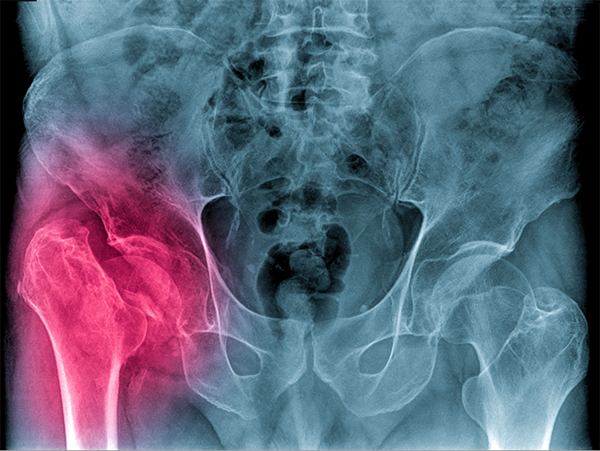

Fractures and dislocations

Pelvic Injuries